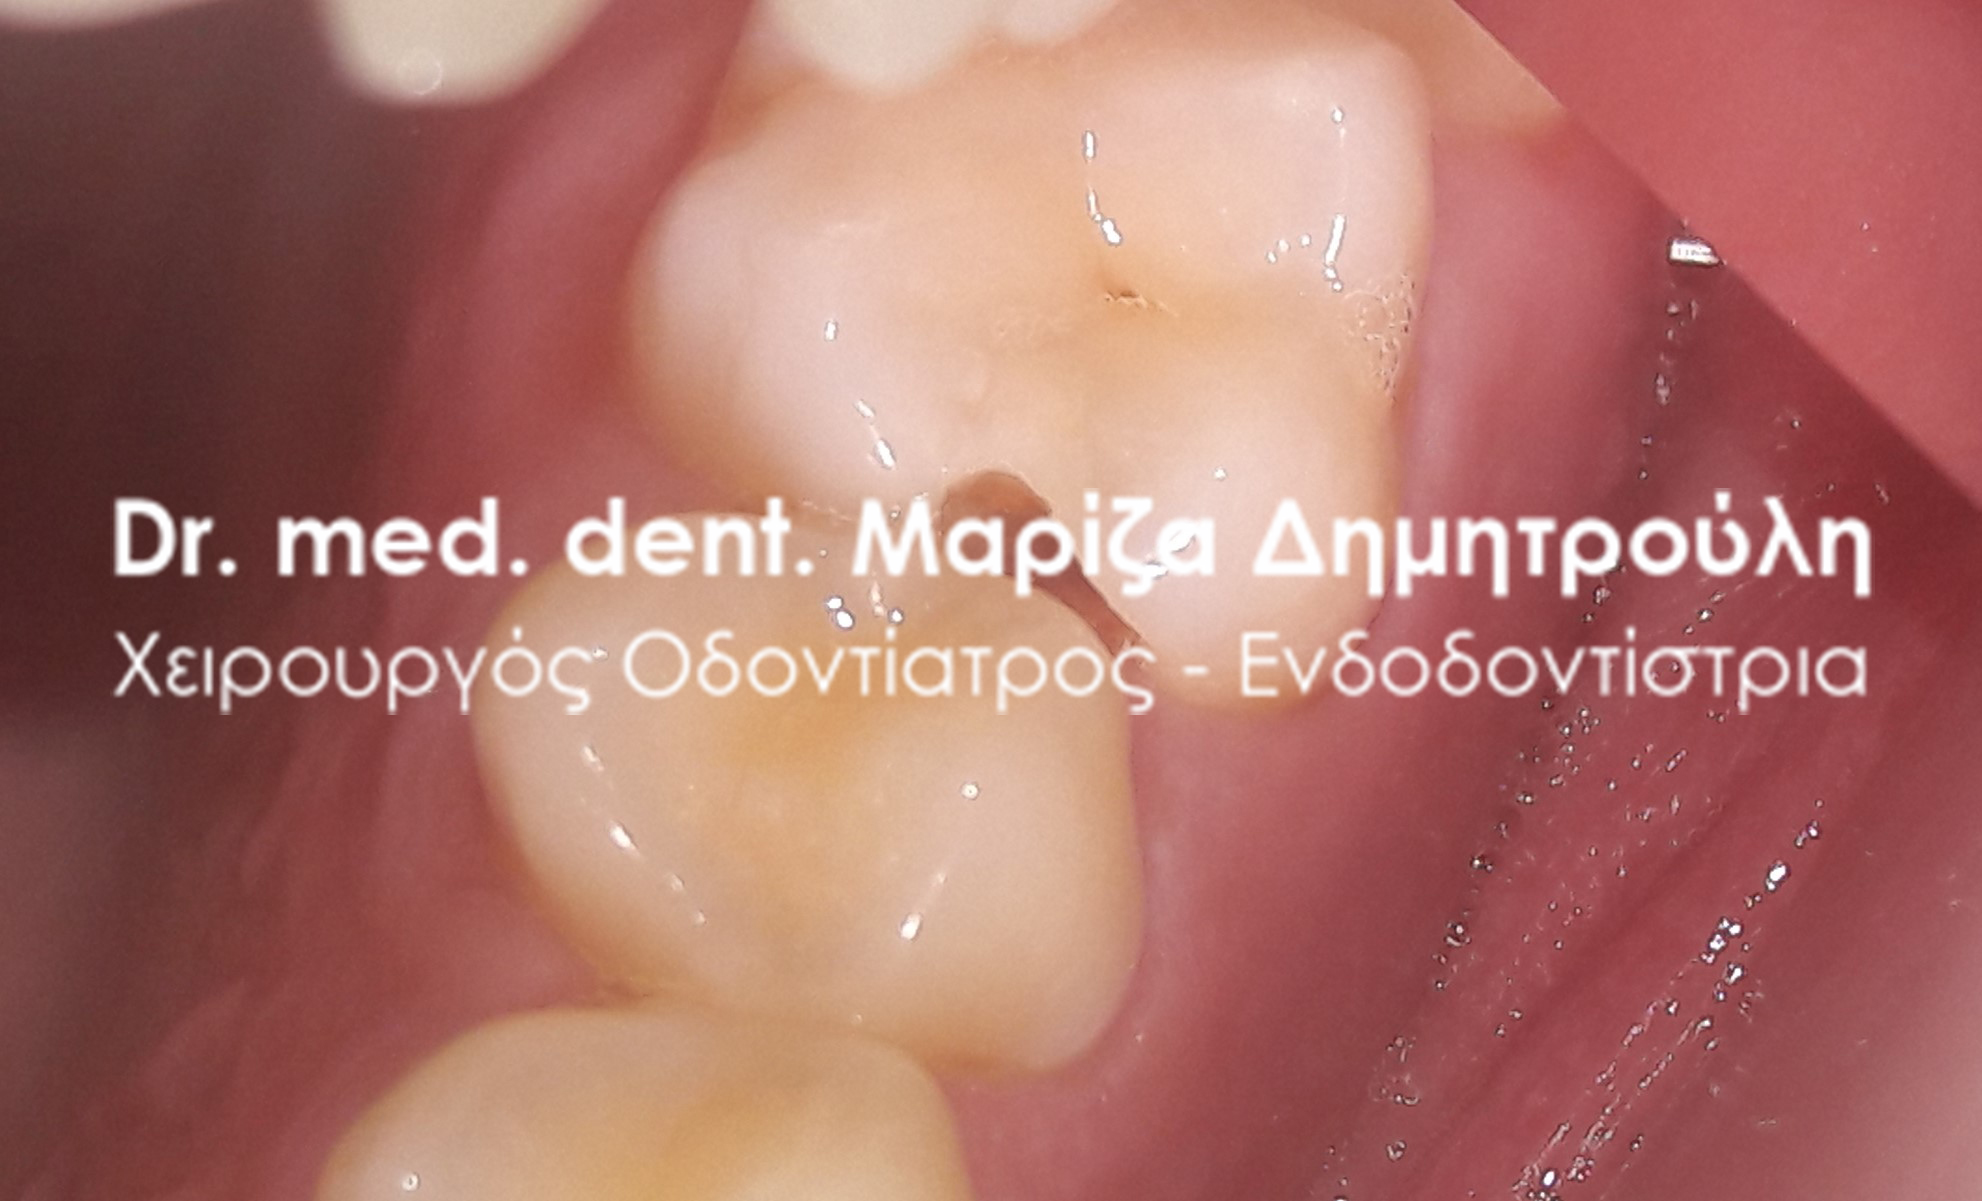

Root canal treatment

BEFORE